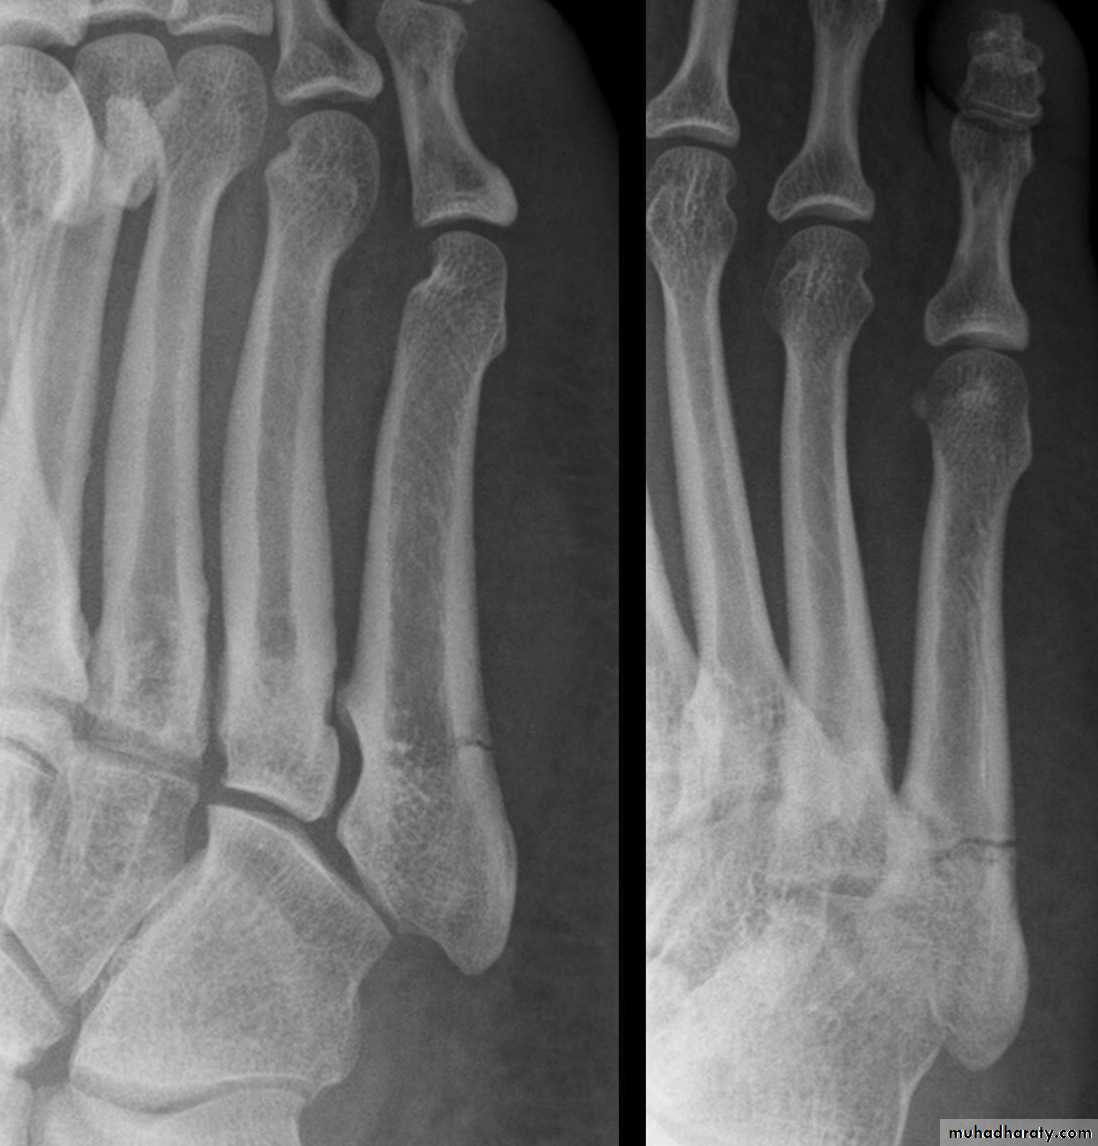

A condition characterized by disruption between the articulation of the medial cuneiform and base of the second metatarsal

unifying factor is disruption of the TMT joint complex

injuries can range from mild sprains to severe dislocations

may take form of purely ligamentous injuries or fracture-dislocations

ligamentous vs. bony injury pattern has treatment implications

Lisfranc Injury (Tarsometatarsal fracture-dislocation